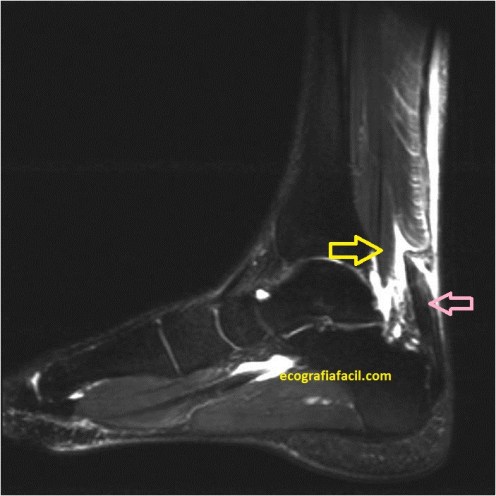

Por último un ejemplo de rotura que te comparo con la imagen de la misma localización en la imagen obtenida previa a la cirugía en RMN:

Estas imágenes corresponden a la misma lesión , del mismo individuo vista con dos técnicas de imagen distinta, las flechas amarillas marcan la zona de rotura casi total…

En la eco se observa ligeramente el líquido anecoico que rodea la lesión y que se ve muy marcado en la imagen potenciada en T2 de la RMN.